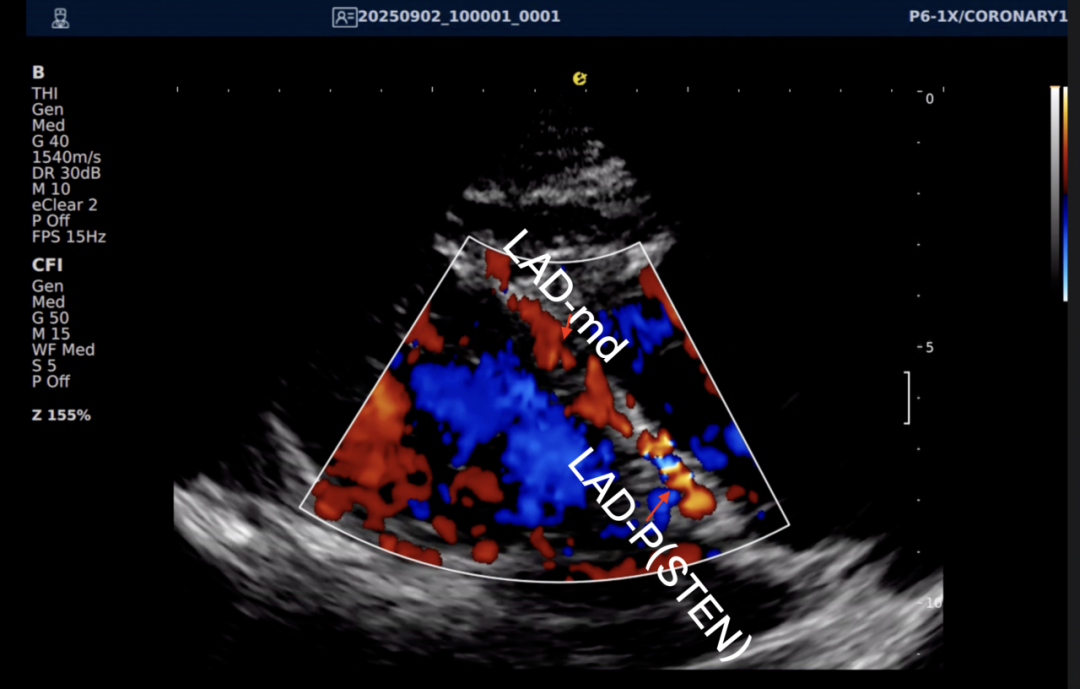

以下为逸超医疗(ESI)设备采集的冠脉图像,清晰展示了其在二维成像、彩色多普勒及频谱多普勒方面的表现:

左右滑动查看更多

心脏冠脉超声

一例胸闷患者,临床采用无创冠脉超声作为初步评估手段,检查中发现:

彩色多普勒:敏感捕捉到局部血流加速现象;频谱多普勒:测得峰值血流速度明显升高,频谱形态异常。

彩色多普勒动态图

彩色多普勒

基于超声提示的异常发现,临床为患者安排了冠脉CTA检查,结果显示前降支近段存在约45%狭窄,与超声提示的血流动力学改变高度一致。

这一病例体现了冠脉超声作为初筛工具的重要价值:它能够无创、实时地评估冠脉血流动力学状态,为后续是否需要进一步影像检查提供重要参考。超声与CTA的协同应用,既能评估结构变化,又能反映功能状态,为临床诊断提供了更全面的信息。